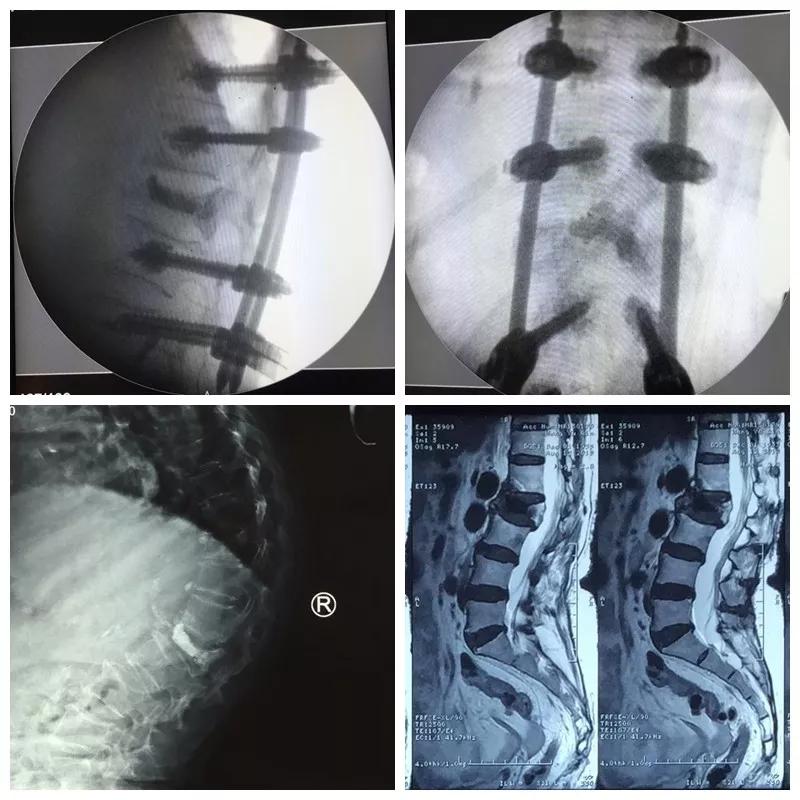

近日,91论坛 骨一科微创团队为一位85岁高龄的患者,运用骨水泥钉道强化技术治疗腰椎骨折后再发后凸畸形,效果满意。

王奶奶今年85岁,1年前摔倒后因骨质疏松导致了腰2椎体压缩骨折,行介入骨水泥治疗,疼痛解除,效果满意。可是后来王奶奶不小心再一次摔倒,驼背明显加重,并又出现了顽固的腰背疼痛和右下肢抽麻,家人把王奶奶送到医院,检查后发现,因为严重的骨质疏松,虽然之前骨水泥加强了骨折椎体,但是没有能阻止骨质疏松的加重,再次摔倒又发生了新的骨折,并且骨折块压住了神经,引起下肢抽麻疼痛。骨一科微创团队经过严谨的术前讨计划与准备,给王奶奶实施了微创手术,一次麻醉同时完成了骨水泥钉道强化矫形、神经减压、新发骨折椎体成形术等三个微创手术,术后驼背畸形纠正、下肢抽麻缓解、腰背骨折疼痛解除,效果理想。老人术后驼背改善了、腰背挺直了,再也不用弯着腰低着头走路了,身高也增加了七八公分,老人开心的说道“我觉得自己又年轻了十几岁”。

郭华院长介绍:骨水泥治疗骨质疏松性压缩骨折已成为常规有效的手术,但是对于严重骨质疏松的患者,单纯骨水泥不能够阻止脊柱后凸畸形的发生,传统椎弓根钉棒系统治疗脊柱骨折矫形效果好,但在严重疏松的骨质里没有足够的把持力,而我们采用的骨水泥强化钉道技术把两者优点结合起来,克服了骨质疏松钉子无把持力的技术难题,而且再加入经皮微创置钉技术,可以完美解决老人的后凸畸形问题。